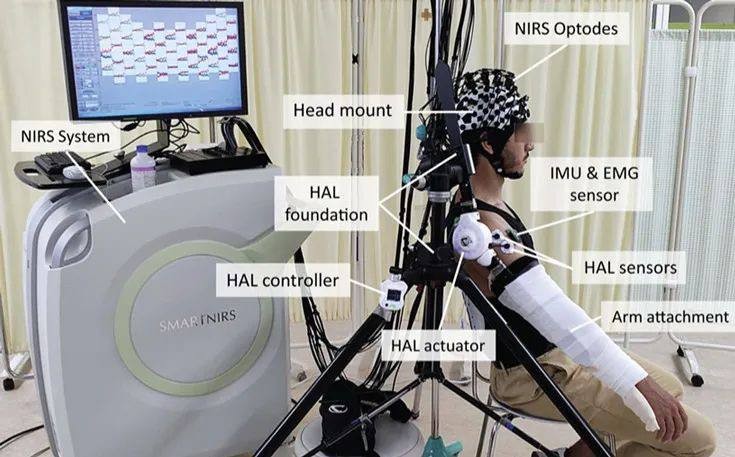

智能医疗辅助设备

项目类型

器械质押区

起投金额

18000USDT

每日释放:0.7

释放周期:43 天

已购: 2777

剩余: 0